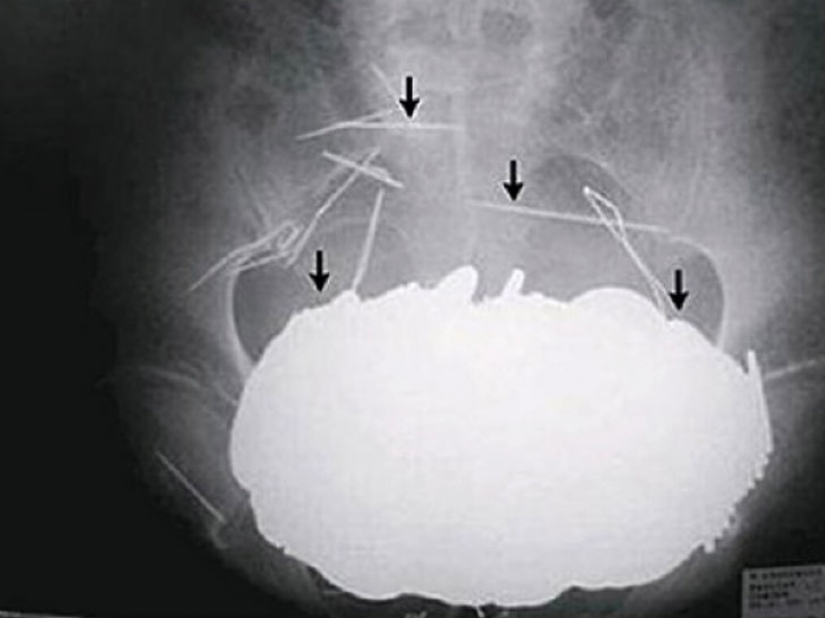

Algunos reclusos están dispuestos a tragarse cualquier cosa con tal de salir de la cárcel, por ejemplo, en el hospital, incluso los resortes del colchón.